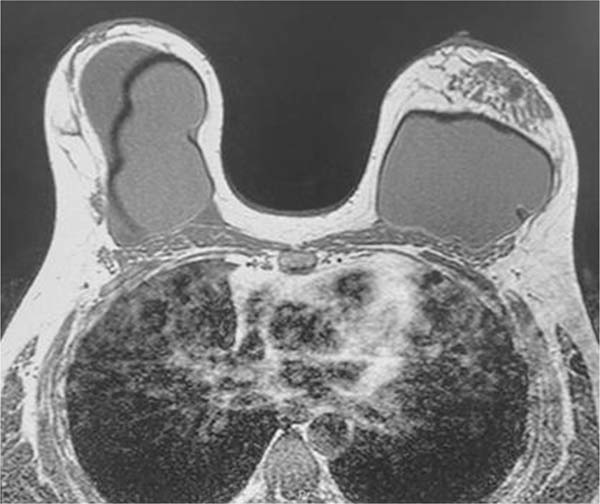

Magnetic resonance imaging showed an extensive intracapsular collection in the right breast with heterogeneous content, associated with enhancement and thickening of the fibrous envelope and capsule, consistent with an inflammatory process and capsular contracture. It was not possible to rule out BIA-ALCL. The Breast Imaging-Reporting and Data System (BIRADS) was 4 (►Fig. 2).